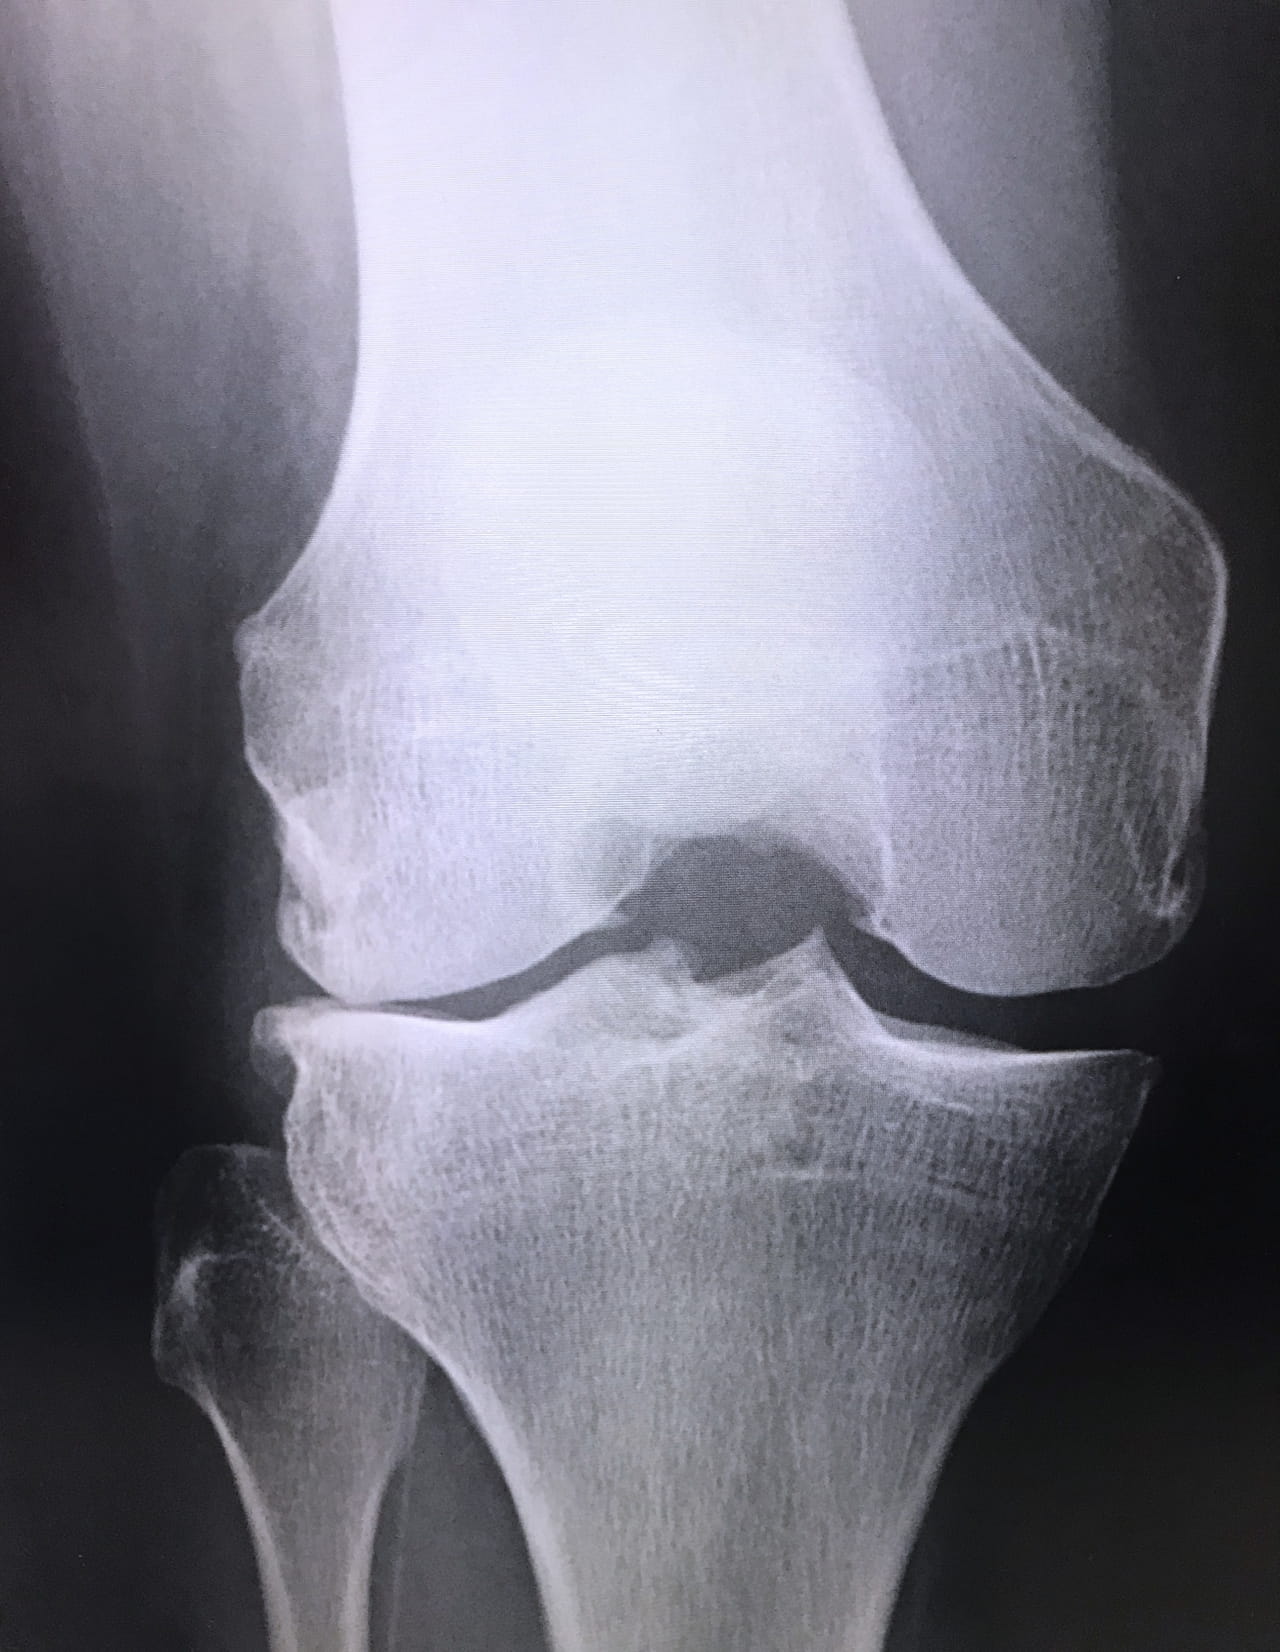

ひざ痛の特徴 骨・軟骨 系

ひざの治療について